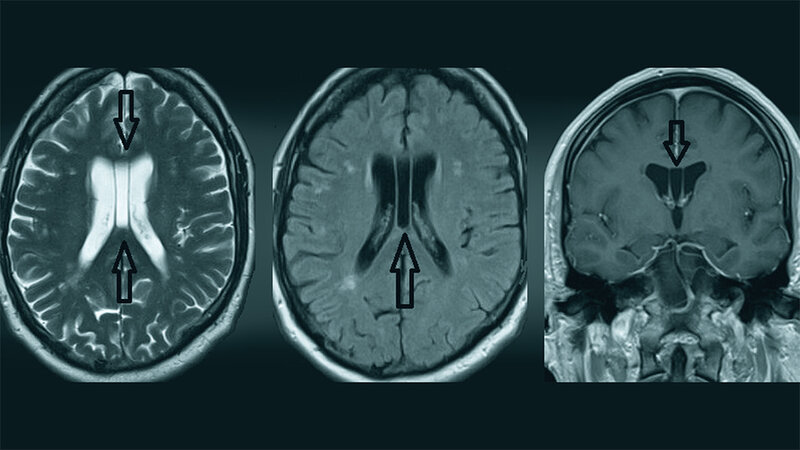

Das Cavum Vergae ist eine anatomische Variante, in der Mittellinie des Gehirns gelegen. Es ist die am meisten vorkommende kavale Variante, während das Septum veli pelluci die seltenere ist. Mittellinienanomalien wie CV können ein unspezifisches Risiko für mentale Veränderungen darstellen.

Cavum Vergae is an anatomical variant located in the midline of the brain. It is the most common type of cavum variation, while cavum septi pellucidi is the rarest. Midline brain abnormalities, such as CV, might represent an unspecific risk for the development of mental disorder.